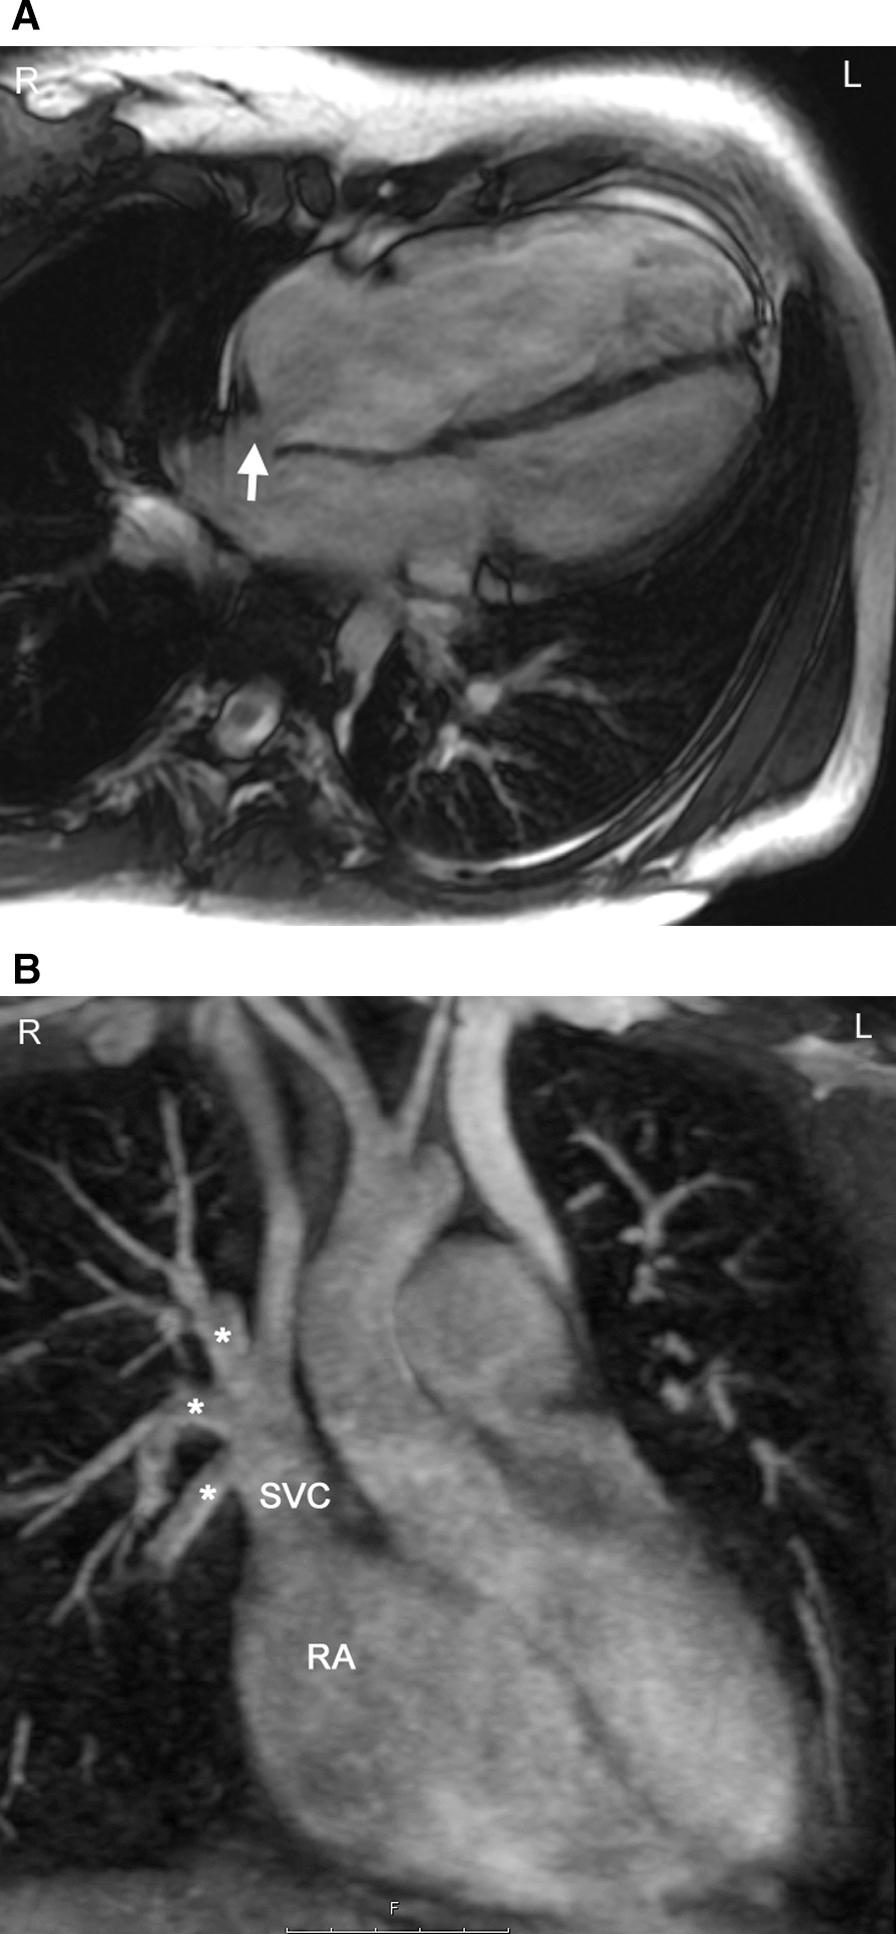

Cardiovascular magnetic resonance (CMR) has been utilized in the management and care of pediatric patients for nearly 40 years. It has evolved to become an invaluable tool in the assessment of the littlest of hearts for diagnosis, pre-interventional management and follow-up care. Although mentioned in a number of consensus and guidelines documents, an up-to-date, large, stand-alone guidance work for the use of CMR in pediatric congenital 36 and acquired 35 heart disease endorsed by numerous Societies involved in the care of these children is lacking. This guidelines document outlines the use of CMR in this patient population for a significant number of heart lesions in this age group and although admittedly, is not an exhaustive treatment, it does deal with an expansive list of many common clinical issues encountered in daily practice.

心血管磁共振(CMR)在儿科患者的管理和护理中已经应用了近 40 年。它已经发展成为评估最小的心脏的宝贵工具,用于诊断、介入前管理和随访。尽管在许多共识和指南文件中提到,但在儿科先天性心脏病和后天性心脏病领域,目前还缺乏一份由众多参与儿童护理的学会共同认可的、最新的、独立的、针对 CMR 使用的大型指南。本指南文件概述了 CMR 在该年龄段的许多心脏病变中的应用,尽管不能说是详尽的治疗方法,但它确实涉及了在日常实践中经常遇到的许多常见临床问题的广泛列表。